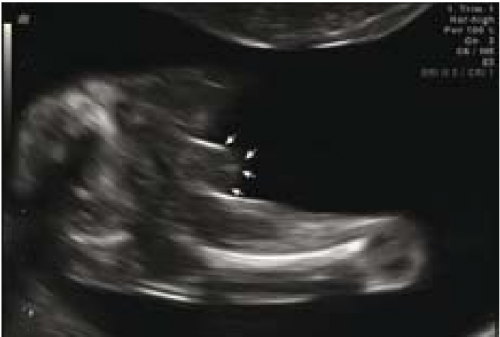

sagittal sign שתואר לראשונה על ידי Emerson וחב'[4] הוא הסמן הסונוגרפי המקובל ביותר לקביעת מין העובר בשלבי ההיריון המוקדמים. העובר נסרק בחתכים סגיטליים בקו האמצע. באזור העכוז הנסרק בחתך זה, ניתן לזהות בליטה שמייצגת את הדגדגן או את איבר המין הזכרי. כאשר כיוון הבליטה כלפי מעלה, מין העובר זכר (תמונה 1) וכיוון כלפי מטה מבטא מין נקבה (תמונה 2). שימוש בסמן סונוגרפי זה אפשר לזהות מין העובר ב-71 אחוז (5\7) מהעוברים בשבוע 10 עד 11.9, אך האבחנה היתה נכונה ב-60 אחוז (3\5) בלבד. דיוק האבחנה עלה עם התקדמות גיל ההיריון ל-75 אחוז, 100 אחוז, 98 אחוז ו-100 אחוז בשבועות 12-13.9, 14-15.9, 16-17.0 ו-18-20.4, בהתאמה[4]. דיווחים רבים אחרים דיווחו על אבחון מין העובר בסוף הטרימסטר הראשון ותחילת השני (14-4) (ראו טבלה 1).

ברונשטיין וחב׳[7] דיווחו שדיוק אבחון מין העובר על ידי אולטרסאונד נרתיקי עולה עם הניסיון, כך שבשנתיים הראשונות לשימוש באולטרסאונד נרתיקי, המין אובחן בדיוק של 76 אחוז ועלה ל-80 אחוז בשנתיים לאחר מכן בין השבועות 14-13 להיריון, ובשבוע 16-15 הדיוק עלה מ-88 אחוז בשנתיים הראשונות לנסיונם ל-96.7 אחוז בשנתיים לאחר מכן. בעבודה זו, מין זכר נקבע על סמך הדגמת מבנה דמוי כיפה (dome sign) המייצג שק אשכים (תמונה 3) בעוד מין נקבה נקבע על סמך הדגמת שניים או ארבעה קווים מקבילים (parallel lines) המייצגים את השפתיים הקטנות והגדולות (תמונה 4) . סימנים סונוגרפיים נוספים בעבודה זו[7] היו הדגמת קו אקוגיני הנמשך מבסיס ועד קצה איבר המין הזכרי ומייצג קו האמצע של הפניס (תמונה 5) וכיוון הפאלוס העוברי (כלפי מעלה מייצג זכר וכלפי מטה נקבה).